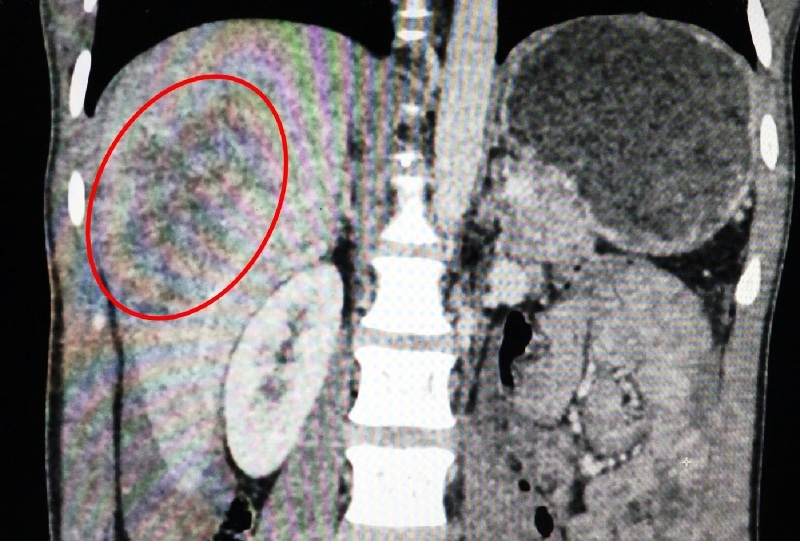

- Anh C. bị ngã chấn thương mạn sườn phải gây vỡ gan độ 3, máu tràn khắp ổ bụng số lượng lớn.